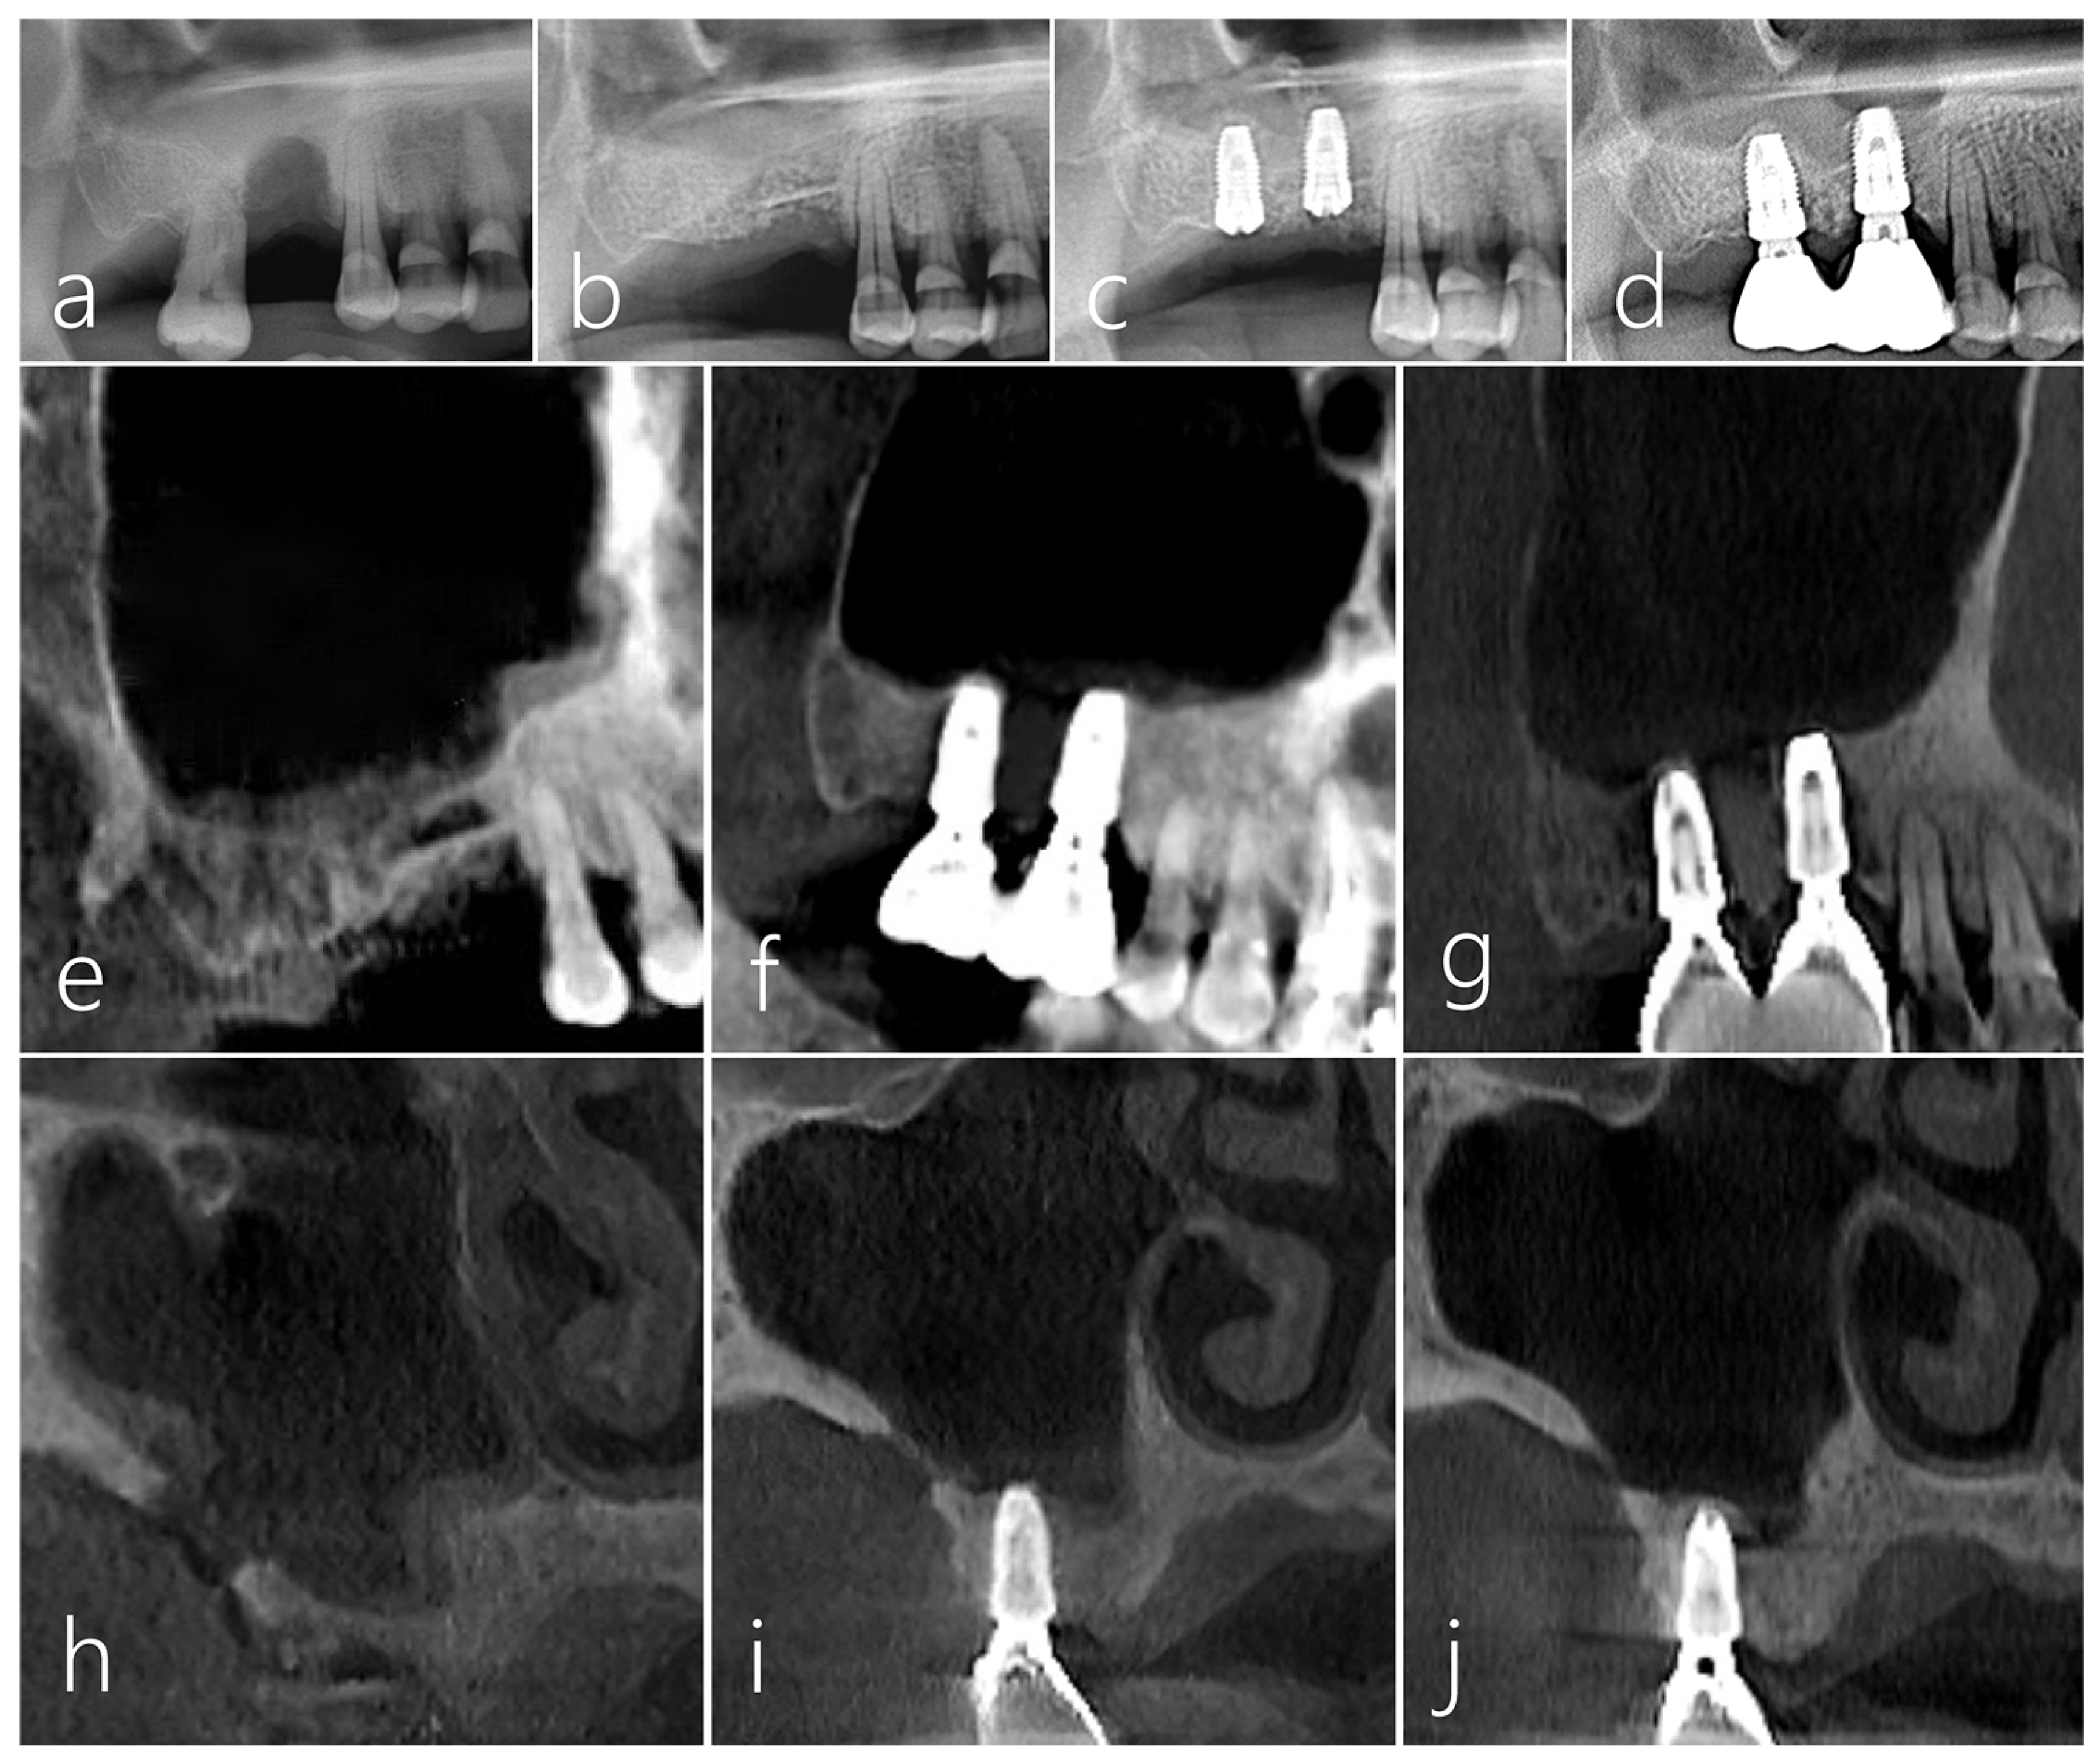

2.3. Case 3

2.4. Case 4